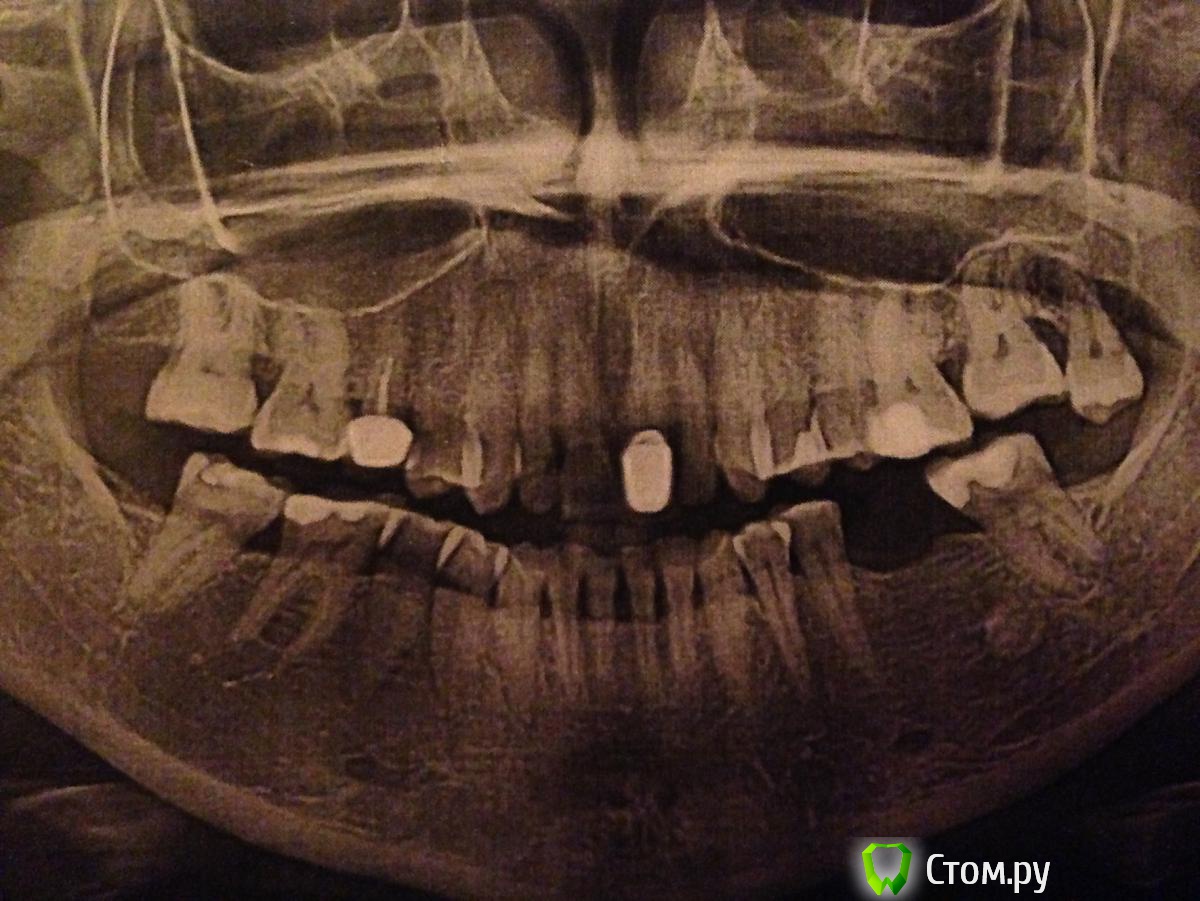

Добрый день!внизу слева собралась ставить имплант,уже ввинчен.Но тут начал выворачиваться нижний передний зуб.Оказалось - возможно исправить брекетами.Но-присутствуют многочисленные клиновидные деффекты внизу от клыка до клыка - и спереди оголяются шейки зубов постепенно - не болят - врач-ортодонт посоветовал заделать все !!клиновидные деффекты внизу и после этого поставить брекеты на нижнюю челюсть. Все остальные врачи не рекомендуют - в силу того что мне уже 40 лет, кость опускается, возможны потом ухудшения - результат непредсказуем.Я уже заделала 2 клыка нижних - остальные зубы пломбировать приостановила.Возможно ли осложнение после брекетов?И какой еще метод выравнивания зуба возможен - коронка или брекеты - вот что мне сказали.Помогите определиться - нужны мне в таком случае брекеты или нет??На снимке - есть по факту изменения - удален верхний зуб мудрости и вживлен имплантт - пока без коронки.

И самое важное - что рекомендуют делать с клиновидными деффектами - и с чего вообще в таком случае начинать?